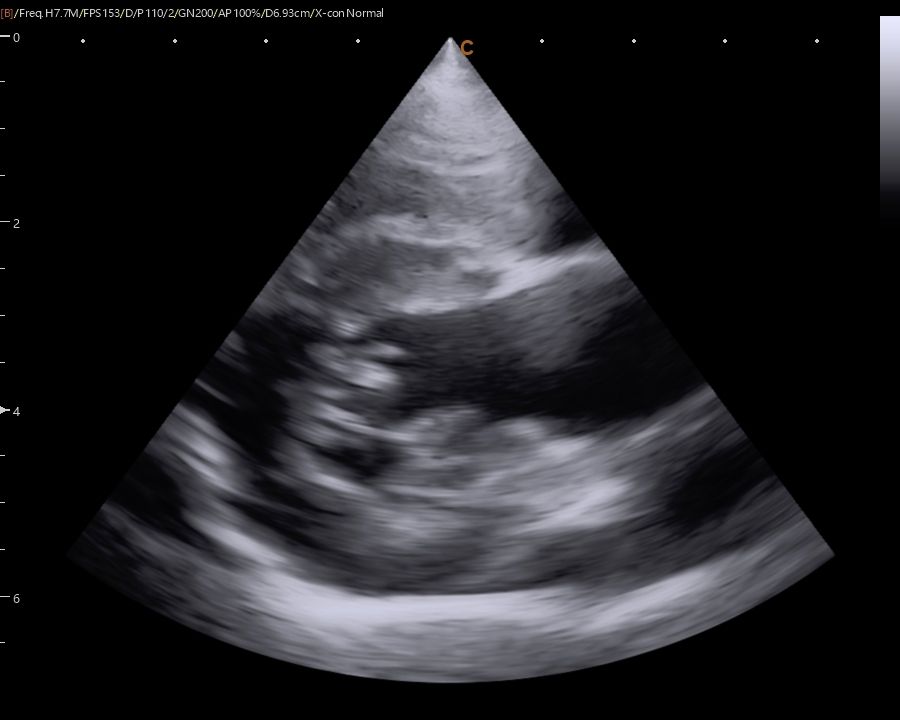

Images from the SonoBook 8 Vet